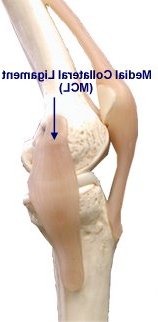

Please annotate this diagram with the site(s) of swelling or tenderness.

Right Knee

Notes: -

Left Knee

Notes:-